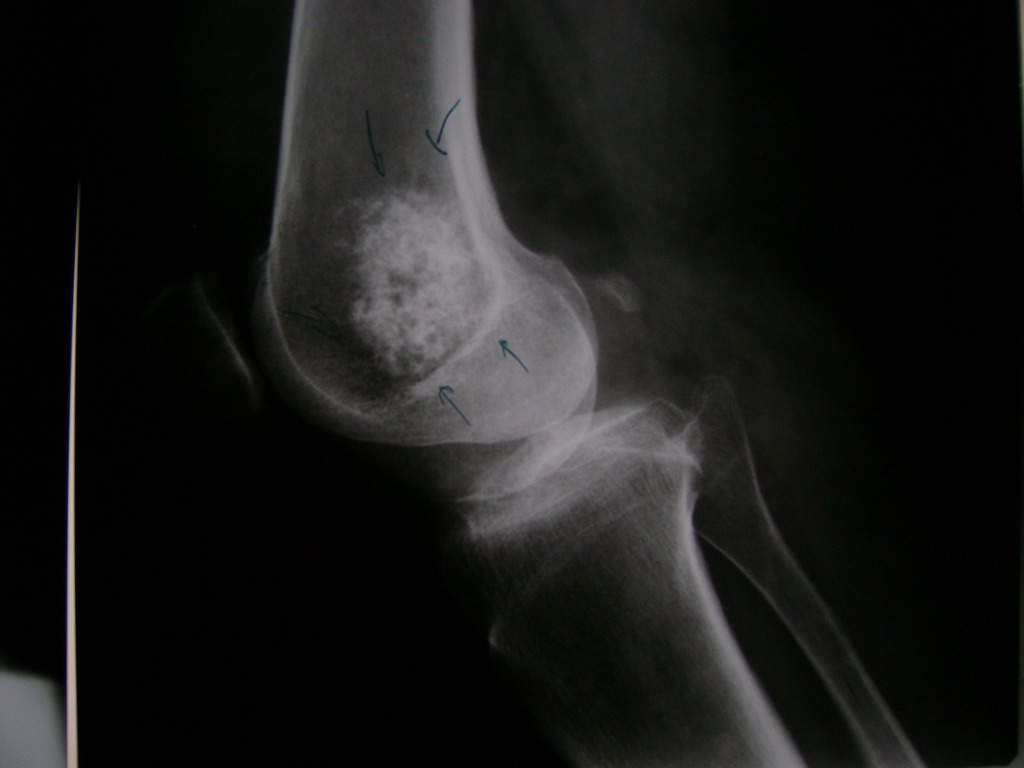

Cirugías de Rodillas

La artroscopia de rodilla es un cirugía en el cual la estructura interna de la articulación es examinada ya sea para realizar un diagnostico o para realizar un tratamiento, este procedimiento se realiza utilizando un instrumento parecido a un pequeño tubo llamado artroscopio.